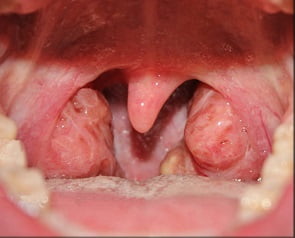

Как выглядит ангина: фото

На фото ниже показано, как проявляется заболевание у взрослых.